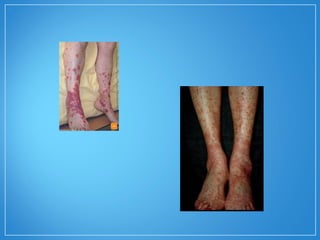

• Manifestações cutâneas : úlceras,

púrpuras palpáveis, nódulos subcutâneos,

pápulas e vesículas. Pioderma

gangrenoso e fenônemo de Raynaud são

raramente relatados.

• Na PAN, são frequentes as manifestações cutâneas,

sendo as mais comuns: livedo reticularislivedo reticularis, fenômeno defenômeno de

RaynaudRaynaud e úlcerasúlceras e alterações isquêmicas das

extremidades dos dedos